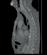

Photon-counting computed tomography (PCCT) promises to revolutionise CT imaging by substantially increasing spatial resolution and iodine contrast conspicuity, reducing radiation dose and beam hardening artifacts, and allowing spectral imaging with multiple energy bins.

Unlike traditional energy integrating detectors which use solid-state scintillators to first convert X-ray photons to light, photon-counting detectors use a semiconductor material to directly convert incoming X-rays to an electric signal in a single step. Each photon gives rise to a voltage that is proportional to its energy, allowing energy discrimination on the basis of voltage comparison. A count can therefore be assigned to the bin that matches the photon’s energy range, hence the name “photon counting”. With enough bins, one can therefore perform spectral analysis of the incoming photon flux, and extract spectral information for quantitation or material decomposition. Since lower energy photons, which produce more contrast information, get equal weighting to higher energy ones, the images have improved contrast resolution.

Prof Roland Bammer, Head of Monash University’s Department of Imaging*, describes this transition. “Remember the times when you were watching sports on a low-res black and white TV with the “bunny ears” on top? Now you can watch events in colour on your 4K TV. This is the paradigm shift in CT that’s currently happening with photoncounting. The ‘colour’ depth isn’t OLED quality yet, and more like on the old CGA or VGA monitors, but it’s there. You can do all the interesting things energy integrators can’t do without dual kV source or kV switching. PCCT does the energy discrimination on the

detector side, and opens up a new field in radiology.”

Although it has long been known that photon counting is the most efficient approach to X-ray detection for CT, developing a direct conversion material which can handle the high X-ray photon flux of CT has been the major challenge. Prof Bammer says “Whether the future of photon-counting CT will lie in cadmium telluride (CdTe), cadmium zinc telluride (CZT), or silicon (Si) semiconductors is still unclear. The jury is still out. The individual vendors seem to have made bets on different semis. Each material has its strengths and weaknesses, and the vendors have learned to leverage the strengths of their material and minimise the impact of its weaknesses. The upcoming RSNA will therefore be very interesting. We might see more vendors entering this space. I believe independent research— outside the corporate labs—is warranted to get to the bottom of it. Once more systems are installed, it will help us to provide the evidence base on real-world performance in clinical settings. Whether it’s the more difficult to manufacture but highly efficient CdTe semis, or the more broadly available, cheaper silicon substrate, is superior, of one thing I am confident: we will see a lot of innovation and new clinical applications in that space in the near future. It’s another big fork in the road for CT, similar to when spiral or multi-detector row CT were introduced. I am therefore very excited about this technology.”

Physicist Dr Christian Schroeter, PhD, who led the effort to develop the direct conversion detector material for Siemens Healthineers, talks to Associate Professor Shalini Amukotuwa, PhD, MB BS, FRANZCR (Head of Diagnostic Neuroradiology and MSK at Monash Health) about the detector and his experience in developing it.

Photon-counting detectors have brought about a paradigm shift in CT imaging. Can you tell us what the main advantages of this technology are, compared to the conventional CT scanners which we are currently using?

There are several technical advantages: higher spatial resolution, elimination of electronic noise, radiation dose efficiency and, last but not least, spectral information, not only in every image, but also everywhere in the image. Improvement in these crucial technical parameters translates to clinical benefits, which we have been working on since the prototype phase. We have already seen that there are certain things that you can only do with a photoncounting CT. For example, a really hot topic is imaging stented coronary arteries. The metallic stents cause a lot of artifacts, due to beam hardening and photon starvation, which obscure the vessel lumen. These patients are therefore often sent to cathlab instead

of CT coronary angiography. Now, with photon-counting CT, we can get really good images of the vessel lumen, to see in-stent details. This is because of the far superior spatial resolution, reduced blooming and beam hardening, and lack of electronic noise, which we can filter out. The spectral information also allows us to obtain material (iodine) images of the vessel lumen, and we can use material decomposition to subtract out any calcified plaques. We are currently exploring whether these images are now accurate enough for catheter angio to be avoided, which will be a big game changer for patients. Another important example is imaging obese patients, and low-dose imaging, where photon counting provides better image quality with less noise because electronic noise is eliminated. The journey has only just begun, and we will continue to see what these technical advantages really mean in clinical practice, since that’s what’s important.

Why did it take so long to develop photon-counting CT scanners? What was the main barrier to overcome?

The direct conversion material for the detector was the main barrier, and we had a long development phase. The project started 20 years ago. We seriously engaged in screening the market of available detector materials around 15 years ago. The first phase was to look at what was already available, then select the best vendor. We identified a company in Japan

The main challenge at that time, 15 years ago, was that most manufacturers used the detector material for gamma cameras, for SPECT, or just spectrometers. The company that we selected already used CdTe detector material for X-ray imaging, although this has a much lower X-ray photon flux than CT. Of all imaging applications, CT has by far the highest X-ray photon flux applied to the detector. The materials which were available then just couldn’t cope with this high flux. There were even scientific papers claiming, based on models, that it may not be possible for CdTe detectors to convert X-rays to photons directly at the typical flux-rates of CT. In the initial prototypes, we could slow down the flux to address this. However, for a clinical full body scanner, you need to be able to work at high flux rates, to be able to deal with any clinical scenario. We were lucky that we came to a point, around 2011, where we could overcome this apparent fundamental hurdle and major impediment which otherwise would have put an end to the project. Another group did actually give

Yes. The solution was based in the CdTe crystal growth itself. You have to go very deep into the very start of the process chain, to the crystal itself, to address the problem of polarisation. You need to understand the whole chain, from crystal growth to image generation, and we saw that many aspects of the crystal growth, for example doping (where tiny amounts of impurities are introduced to alter the crystal structure), the temperature treatment, and the electrodes that we applied, needed to match the bulk material. We had to bring all these pieces together, and understand the signal that comes out of the detector material to design the electronics, the application specific integrated circuit, accordingly. But the trick was really in the first steps, and it was quite a basic one.

Volume 18 No 4 | September 2022 19

So those steps reduced the amount of charge (hole) trapping in the detector material, which is the cause of depolarisation?

Yes. The assumptions, which were made in the models which showed that building a CT detector from CdTe would not be possible, were not as simple as initially thought. The models that we now have, based on our empiric observations and better understanding of the detector material, are quite different. It turns out that hole trapping is not such an issue after all! In fact, it never was a fundamental issue for CdTe, but back then, we didn’t have the knowledge and understanding to have this insight and confidence. Now, the fact that there is a clinical whole-body photon-counting CT shows that the argument that CdTe can’t be used as a detector just doesn’t hold true. We have also seen that there is another company in Canada which is stepping into prototyping at a clinical level using a detector with similar material, CZT. I’m therefore confident that they have also overcome this basic hurdle.

Can silicon detectors work for photon-counting CT?

Spatial resolution is the major weakness of silicon-based detectors, and also radiation dose efficiency because of lower absorption which is due to the lower atomic number. With any detector material, you can, with the right system design, bring out one specific parameter and excel at it. For example, extremely high spatial resolution, energy resolution, or dose efficiency. That is nice for a scientific paper or a prototype, but not for a clinical product. You need to have a holistic approach, and bring together and harmonise these parameters for a clinical scanner. You also need scan speed, which is underestimated, and not just for cardiac applications. Dose efficiency and spatial resolution maybe the most important, but then speed, and then energy information. We worked on this integration and harmonisation for 10 years, starting with prototypes scanners and ending with the final product. In my understanding and firm opinion, silicon just can’t do this.

Do you need more than four energy bins?

We will see. It felt like the end of the journey when we launched the clinical scanner, now it seems like it’s just the beginning. We will see what the clinicians and researchers will find out. But right now, in my opinion, even if you have one threshold, you already have most of the advantages of photon counting, like dose efficiency, high spatial resolution, and absence of electronic noise. If you have two energy bins, you can do iodine separation. With a third bin, then you can do crazy stuff, with new contrast agents such as gadolinium and gold particles, which have a k-edge. It is possible then to make an additional energy separation, but this is a very early, pre-development research topic. The scanner has a fourth bin, so you are future proof in case somebody invents something where you need it. More bins than that are superfluous.